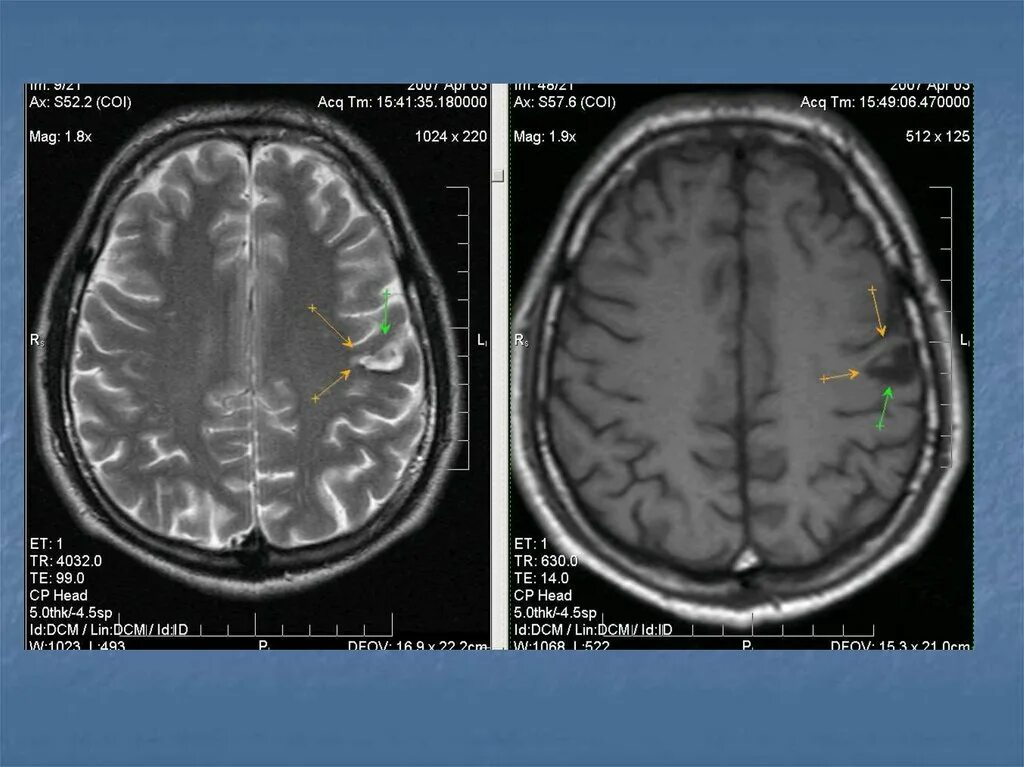

Диффузные изменения вещества головного мозга